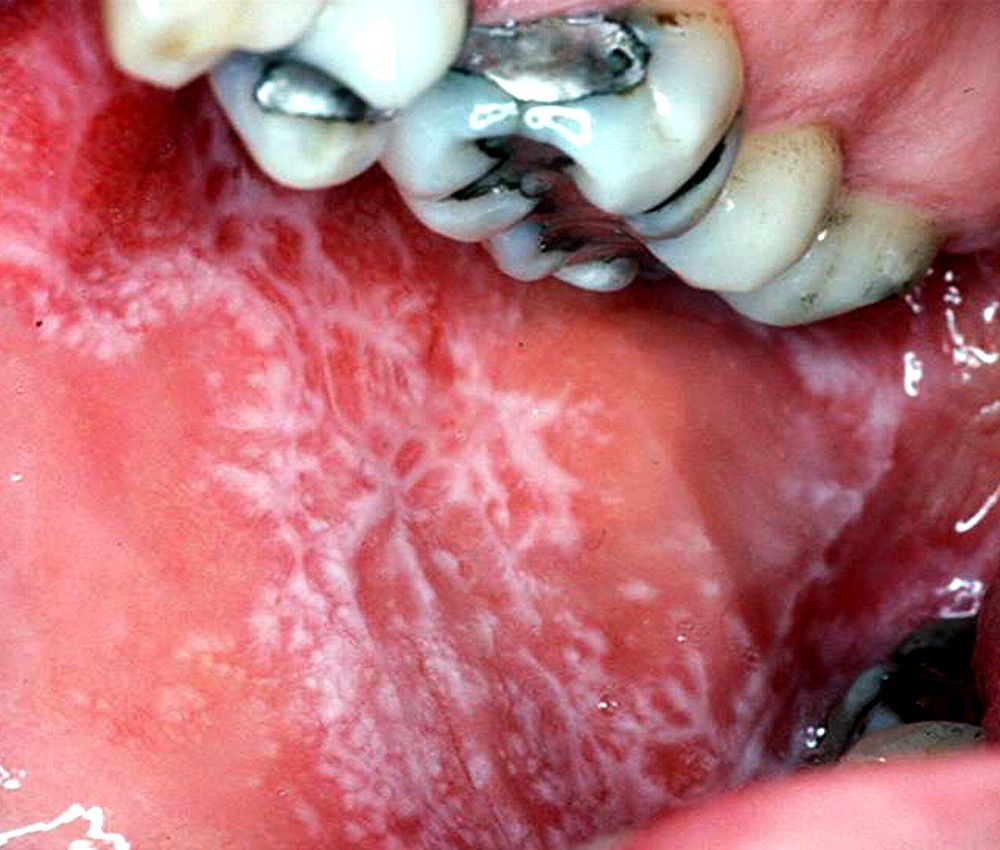

Smokeless Tobacco Lesions termed snuff dipper’s lesion, snuff pouch and spit tobacco keratosis among other terms, smokeless tobacco. as smokeless tobacco is placed intraorally, these compounds can lead to dysplastic changes in the oral mucosa. while carcinogenicity of smokeless tobacco (st) to humans is well established the oral lesions that precede development of. the mechanical trauma caused by chewing or holding smokeless tobacco products can lead to the formation of pre. causative linkages of smokeless tobacco (slt) use with oral potentially malignant disorders and cancers of oral cavity,. it provides suggestive evidence of an association of snuff use with gingival recession and attachment loss,. termed snuff dipper’s lesion, snuff pouch and spit tobacco keratosis among other terms, smokeless tobacco.